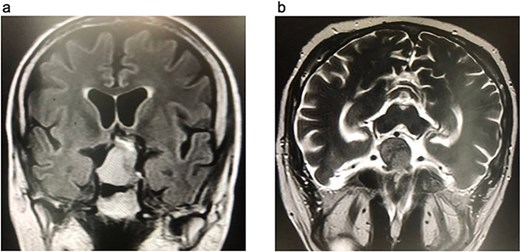

The preoperative laboratory tests for the patient revealed a white blood cell count (WBC) of 12.7 × 109/L, hemoglobin (HGB) of 16.1 g/dL, glycated hemoglobin (HbA1c) of 6.44%, C-reactive protein (CRP) of 1.87 mg/L, and serum creatinine of 0.99 mg/dL (Table 1). A diagnosis of Cushing's disease (CD) was made based on a significantly elevated adrenocorticotropic hormone (ACTH) level of 318 pg/mL, a markedly elevated cortisol level of 1750 nmol/L, and an abnormal 1 mg dexamethasone suppression test result of 1261 nmol/L. Magnetic resonance imaging (MRI) revealed a pituitary macroadenoma measuring 35 × 27 × 25 mm, located in the sellar region, replacing the pituitary gland, and extending into the suprasellar space. The tumor exhibited a heterogeneous appearance with cystic changes, caused mild compression of the optic chiasm, and resulted in thinning of the sellar floor, abutting nearby structures, including the cavernous sinuses, internal carotid arteries, and posterior cerebral arteries, without evidence of invasion or aggressive features (Fig. 1). Cerebral computed tomography angiography (CTA) revealed the tumor abutted the A1 segments of the anterior cerebral artery anteriorly, the cavernous sinuses and internal carotid arteries laterally, and the basilar tip and posterior cerebral arteries posteriorly, all without encasement. Additionally, the sphenoid sinuses showed complete sellar-type pneumatization.

Brain MRI. (a) FLAIR coronal section. (b) T2WI axial section, show pituitary macroadenoma, measuring 35 × 27 × 25 mm. The sellar mass expands the sella and extends into suprasellar region, exhibiting a heterogeneous signal. It is in contact with optic chiasm and partially encases internal carotid artery (ICA).